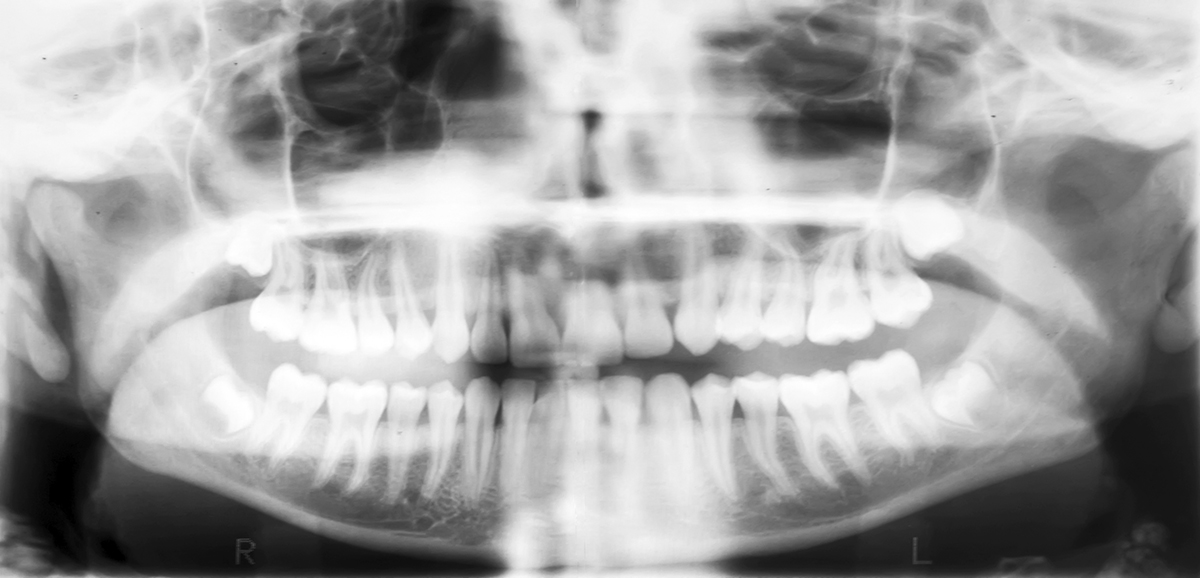

What Does A Cavity X Ray Look Like . You can also see a regular cavity on the left side of the. The root cavity is on the right side of the tooth. There are three things to look out for in the. This can inform their treatment plan. Cavities on the chewing surfaces of your teeth are hit and miss. Each type serves a specific purpose, such as detecting cavities, bone loss, or impacted teeth. Meanwhile, a typical filling shows up as a much brighter spot on the tooth. Represents solid structures and shows up as white.